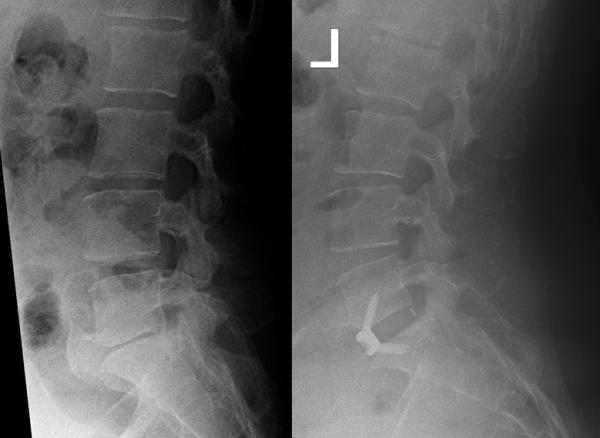

ArcadiusXP L® von der Firma Aescualp ist ebenfalls ein ALIF-Cage für den vorderen Zugang. Wie bei jedem Eingriff ist es wichtig, die Lordosewinkel der Bandscheibenfächer und die umgebende Anatomie zu verstehen, um sich auf den anterioren Eingriff vorzubereiten. Zur Messung der Bandscheibenhöhe und der in Frage kommenden Implantatgröße,werden präoperative Röntgenaufnahmen angefertigt. An den Röntgenaufnahmen wird die Impantantgröße kalkuliert. Dabei gilt es auch durch die Herstellung der ursprünglichen Bandscheibenhöhe die Nervenkanäle wieder zu öffnen und nerven zu entlasten. Der Arcadius ist die ideale Kombination aus erhöhter Stabilität, verbesserten Bildgebungseigenschaften und operationsspezifischer Simplizität. Durch die zusätzliche osteokonduktive PLASMAPOREXP Beschichtung wird sowohl die Stabilität des Implantates verstärkt, als auch dessen Bildgebungseigenschaften verbessert. Das einzigartige Implantat-Design und die flexiblen Instrumente gewähren ein einfaches Einsetzen der Schrauben in allen indizierten Level und anspruchsvollen Patientenanatomien.

Patient mit ausgeprägter erosiver Osteochondrose LWK 4/5 und 5/S1 und deurlicher Verminderung der Bandscheibenhöhe.